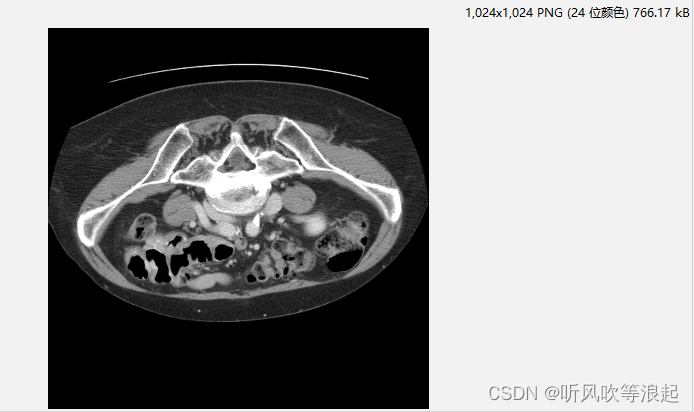

转换生成的数据如下: